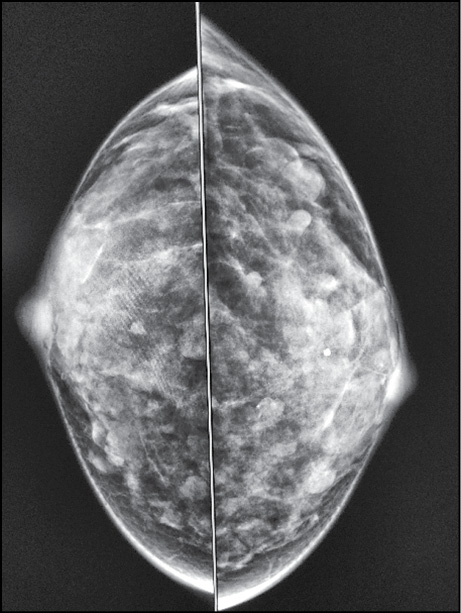

A 38-year-old patient complained of 1-month itching of the right nipple and skin discoloration. Breast ultrasonography and mammography findings (Figs. 5 and 6) were normal. The breast was examined by contrast-enhanced MRI. The early postcontrast series revealed a right nipple mass homogeneously accumulating a contrast agent (Fig. 7). A parametric map showed a nipple mass with rapid contrast enhancement and subsequent elimination, a type III graphic curve (Fig. 8). Morphological verification revealed nipple adenoma.

Figure 5. A nipple adenoma: mammography (mediolateral oblique projection).

Figure 6. A nipple adenoma: mammography (craniocaudal projection).